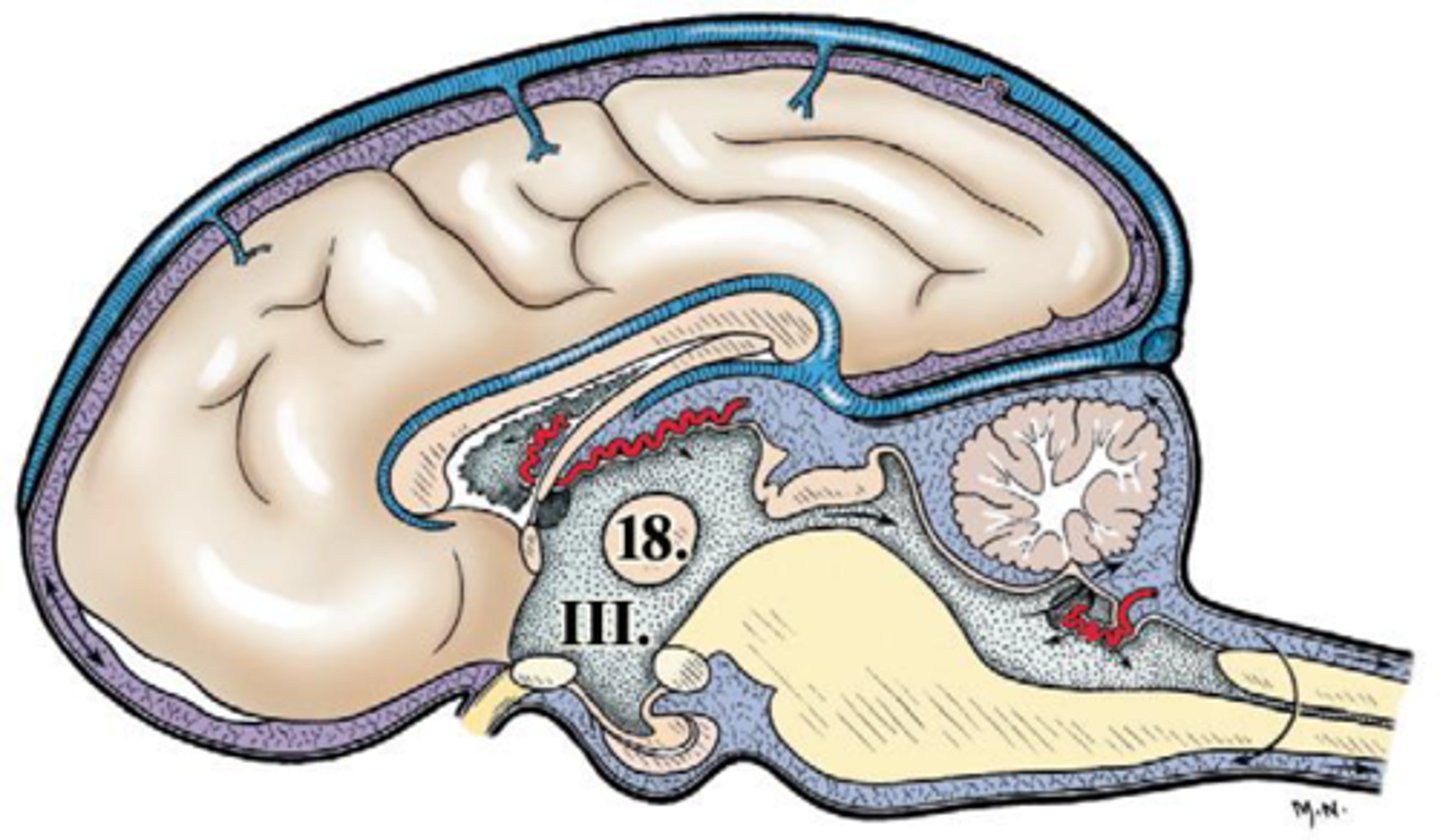

ventriculus tertius

III

ventriculus quartus

IV

adhesio interthalamica

18